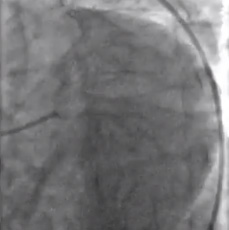

Diagnóstico

• El ECG mostró bradicardia sinusal con antiguo infarto inferior.

• El angiograma coronario izquierdo mostró ostium separado de las arterias DAI y circunflejas izquierdas.

• La arteria circunfleja izquierda presentaba flujo de TIMI-2. Existía una estenosis subtotal y de elevado grado en la parte proximal.

• Con cierta dificultad, se usó un catéter guía de 6F de soporte adicional para realizar la canulación de la arteria circunfleja izquierda.